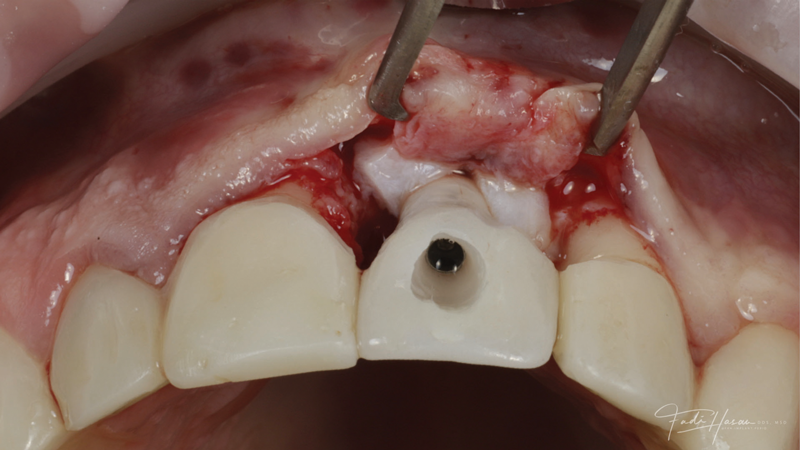

(3.) The crown was removed, and a partial thickness flap was reflected using a papilla-sparing incision design, which revealed that the implant was positioned too far facially and that its body was visible through a very thin layer of bone.

Figure 3

(4.) The crown was removed, and a partial thickness flap was reflected using a papilla-sparing incision design, which revealed that the implant was positioned too far facially and that its body was visible through a very thin layer of bone.

Figure 4